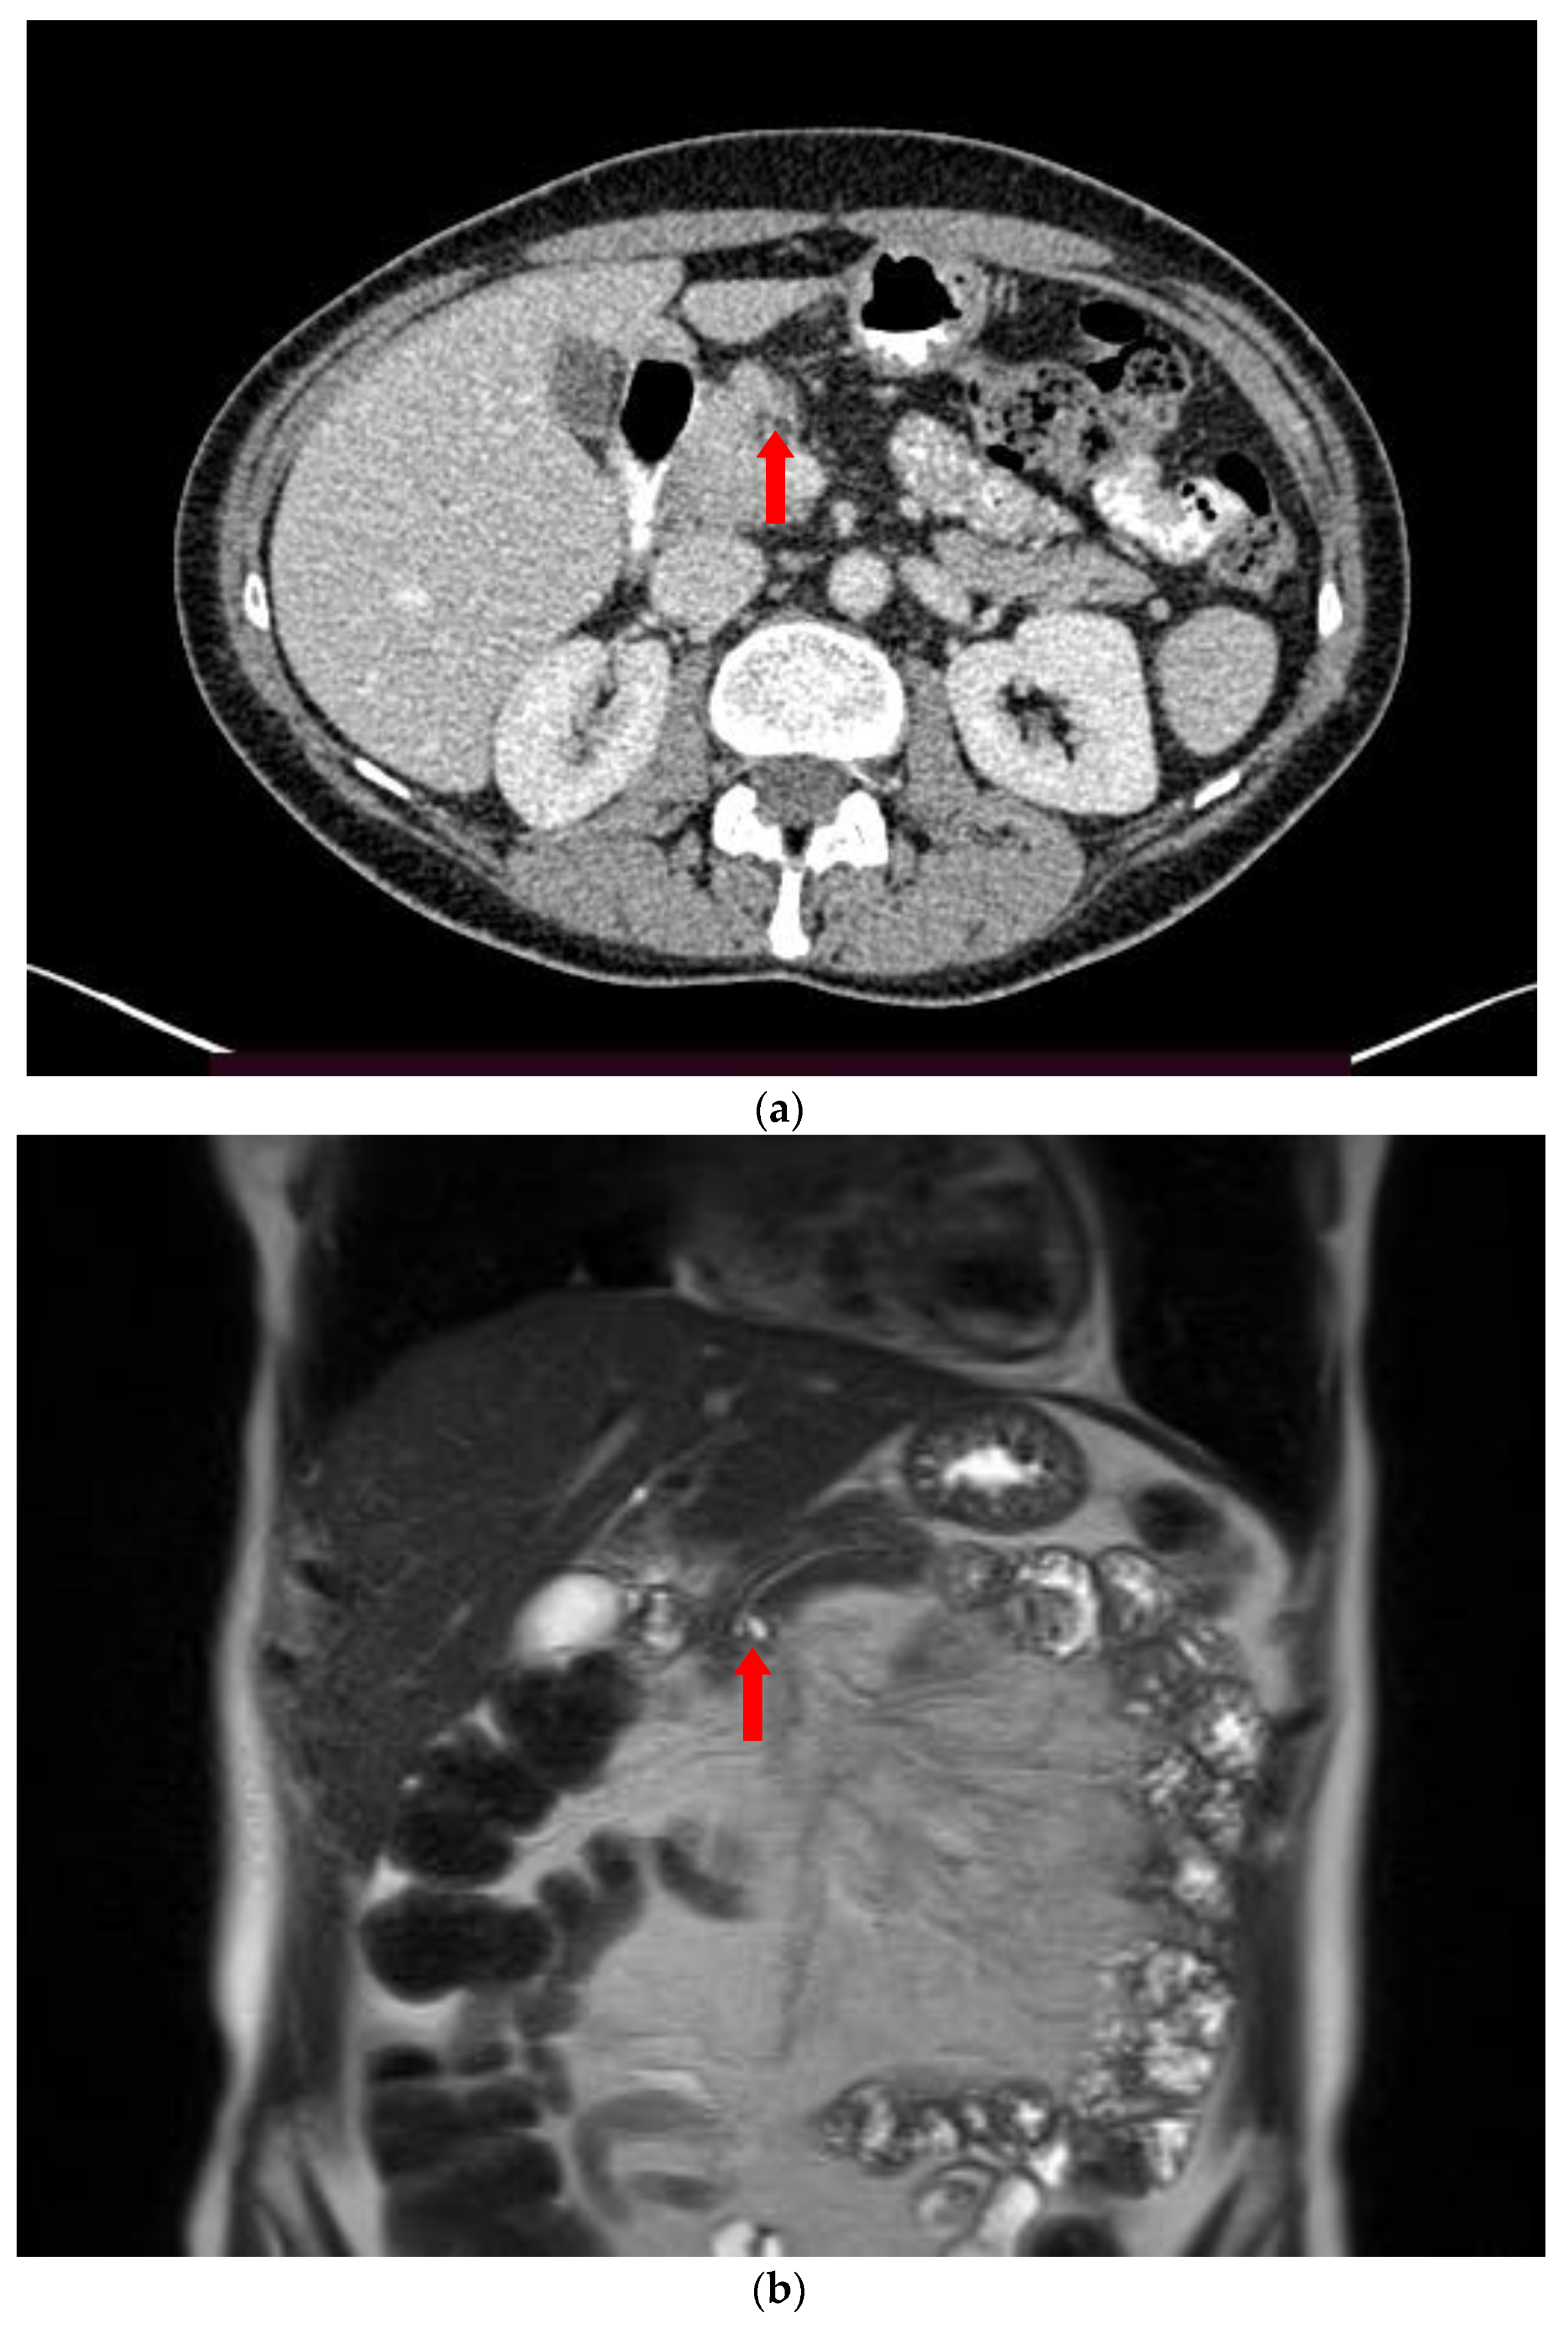

2. Imaging Findings

7. Histopathological Correlation

8. Concomitant Pancreatic Neoplasms